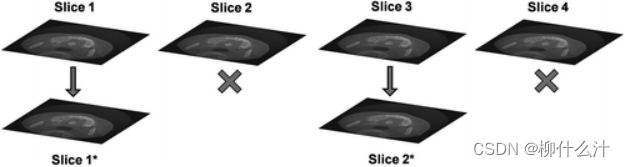

增加切片间隔(SI)意味着丢弃一部分切片(在这里是50%)。剩下的那部分切片等于体素大小除以SI(例如0.25毫米的体素大小,0.5毫米的切片间隔:剩下50%的切片)。切片总数随着SI的增加而减少,但每个切片内的图像质量不会改变(例如,切片1与切片1*是相同的)。